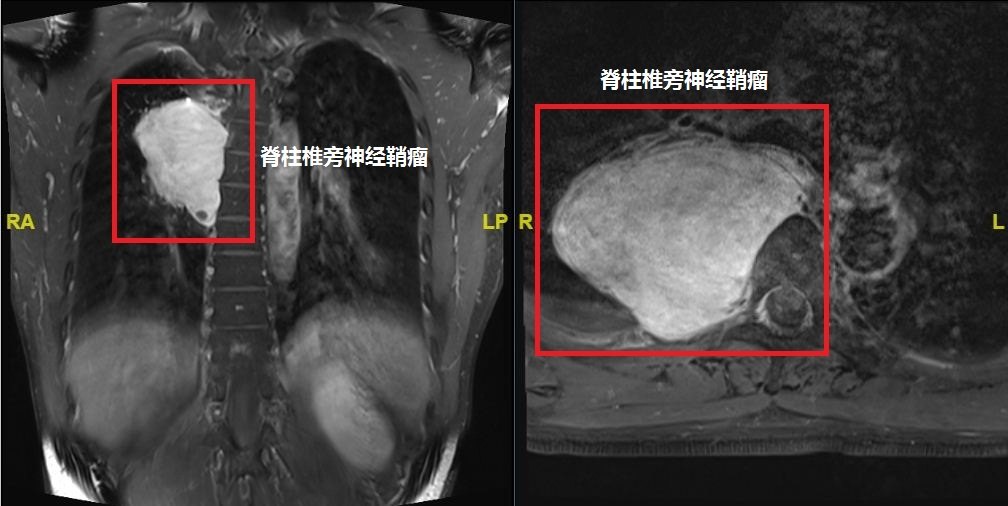

脊柱椎管内外沟通性神经鞘瘤上海肿瘤医院神经外科

神经外科-脊柱肿瘤诊治中心脊柱常见部位神经鞘瘤 - 微医(挂号网)